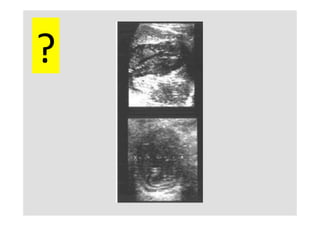

ClassificaKon	échographique

Gharbi

univésiculaire	 décollement	 mulKvésiculaire	 pseudotumoral	 calcifié

?